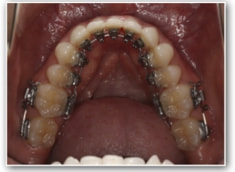

治療法:裏側の矯正(リンガルブラケット:舌側矯正)

治療開始1年後